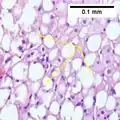

The primary characteristic of MASLD is the accumulation of lipids in the liver, largely in the form of triglycerides.[19] However, the mechanisms by which triglycerides accumulate and the reasons that accumulation can lead to liver dysfunction are complex and incompletely understood.[19][47][48] MASLD can include steatosis along with varied signs of liver injury: either lobular or portal inflammation (a form of liver injury) or ballooning degeneration. Similarly, NASH can include histological features such as portal inflammation, polymorphonuclear cell infiltrates, Mallory bodies, apoptotic bodies, clear vacuolated nuclei, microvesicular steatosis, megamitochondria, and perisinusoidal fibrosis.[16] Hepatocyte death via apoptosis or necroptosis is increased in MASH compared with simple steatosis, and inflammation is a hallmark of MASH.[32]

NASH (inflammation) and fibrosis stage 1

NASH (inflammation) and fibrosis stage 1 NASH (inflammation) and fibrosis stage 2

NASH (inflammation) and fibrosis stage 2 Lobular inflammation

Lobular inflammation

NAFLD comprises two histological categories: NAFL, and the more aggressive form NASH. The presence of at least 5% fatty liver is common to both NAFL and NASH, but the features of substantial lobular inflammation and hepatocyte injuries such as ballooning or Mallory hyaline only occur in NASH. The majority of NAFL cases show minimal or no inflammation.[3][5][7] Pericentral and perisinusoidal fibrosis occur more often in adult-onset NASH, whereas portal fibrosis is more common in children with the disorder. NASH represents a more advanced stage of NAFL and is associated with poor outcomes such as cardiovascular events, cirrhosis, or hepatocellular carcinoma. ICD-11 does not use the term NAFL as it was deemed confusing with the family of disorders NAFLD. The preferred descriptions are instead: MAFLD without NASH or simple steatosis and "NASH". Also, the modifier with or without fibrosis or cirrhosis completes the diagnostic description.[3][7]